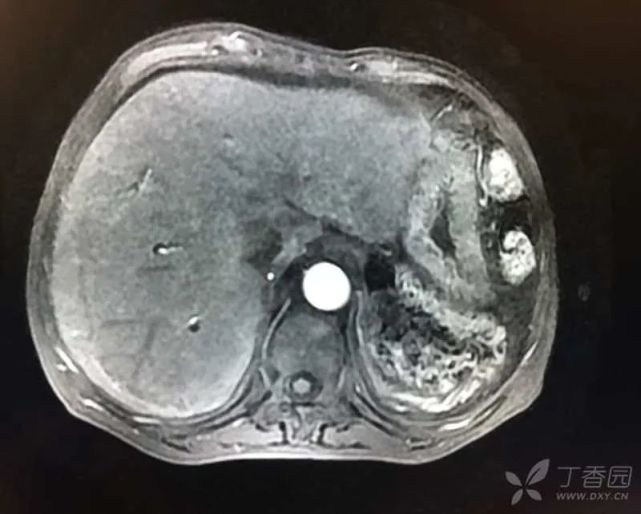

病毒全套、EBDNA、CMVDNA、ANCA、自身免疫系列、自身免疫性肝病谱、甲状腺功能均无明显异常,K-F 环阴性。MRCP:胆囊结石伴胆囊炎表现,胆总管轻度扩张,壁稍强化(炎性改变?),脾切除术后改变,肝脏再生结节形成可能性大,双肾多发小囊肿征,少量腹水(图 2)。

图片

(图 2 MRCP 检查结果)